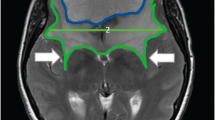

The location of atypical and malignant tumors significantly influences the RFS in the present study, in agreement with Kane et al.5. Dziuk et al. reported that the parasagittal-falcine lesions present with the highest recurrence rates through reviewed recurrent atypical and anaplastic tumors29. In our study, the RFS is decreased significantly in patients with parasagittal and posterior fossa tumors (HR = 2.2, p = 0.005). These tumors often were attached to or invade the sinus wall of the superior sagittal sinus or transverse sinus. This tumor location increases the difficulty of radical resection and may obscure residual tumor due to sinus enhancement, which may mislead the surgeon on the completeness of the tumor resection.